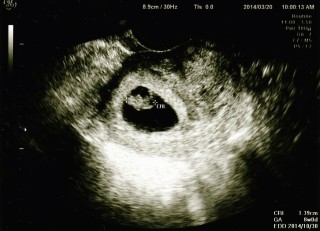

CRL1.39cm

7W時にはただの楕円にしか見えなかったけれど、頭と手足がなんとなくわかる位まで成長してくれました。

旦那様は「ふなっしーみたい」と大喜びでした。

心音もしっかり聞こえました。

切迫流産などで心配な毎日…

元気に育ってくださいお願いします(/ _ ; )